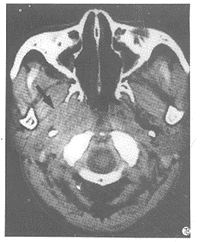

詢問病史 包括年齡、性別、病程長短、症狀輕重、治療效果,以及有無鼻、咽、喉、口腔等器官受累的臨床表現,或發熱,消瘦等全身症狀。2、臨床檢查 首先注意觀察兩側頸部是否對稱,有無局部腫脹,瘺管形成等現象。然後進行頸部捫診。檢查時受檢者頭略低,並傾向病側,使頸部肌肉鬆弛,便於腫塊之捫摸。檢查時注意腫塊之部位、大小、質地、活動度、有無壓痛或搏動,並應兩側對照比較。如前所述,成人頸部腫塊應考慮轉移性惡性腫瘤可能,因此,應常規檢查耳鼻咽喉、口腔等處,以便了解鼻咽、喉等處有無原發病灶。必要時可作鼻內窺鏡或纖維鼻咽喉鏡檢查。3、影像學檢查 頸部CT掃描除可了解腫瘤部位、範圍外,並有助於明確腫塊與頸動脈、頸內靜脈等重要結構的關係,為手術治療提供重要參考依據,但較小之腫塊,常不能顯影。為查找原發病灶,可酌情作鼻竇、鼻咽和喉側位等X線拍片檢查。對於頸部鰓裂瘺管或甲狀舌管瘺管,可行碘油造影X線拍片檢查,以了解瘺管走向和範圍。4、病理學檢查(1)穿刺活檢法:以細針刺入腫塊,將用力抽吸後取得的組織,進行細胞病理學檢查。適用於多數頸部腫塊者,惟其取得之組織較少,檢查陰性時,應結合臨床作進一步檢查。(2)切開活檢法:應慎用。一般僅限於經多次檢查仍未能明確診斷時。手術時應將單個淋巴結完整取出,以防病變擴散。疑為結核性頸淋巴結炎時,切開活檢後有導致傷口經久不俞愈可能,應注意預防。對於臨床診斷為涎腺來源或神經源性良性腫瘤者,由於腫瘤位置較深,術前切開活檢有時不易取得陽性結果,卻有使腫瘤與周圍組織粘連,增加手術困難之弊端,故一般於手術摘除腫瘤後再送病理檢查。